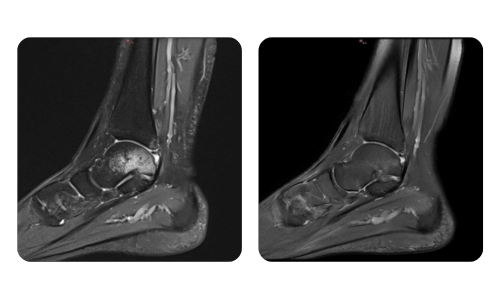

Progresul pacienților noștri, măsurat înainte și după terapia hiperbară, reflectă eficiența și impactul pozitiv al tratamentului. Descoperă rezultate documentate ale terapiei hiperbare la clinica Hyperbarium Oradea, bazate pe evaluări clinice și date obiective care evidențiază îmbunătățiri semnificative în diverse afecțiuni.